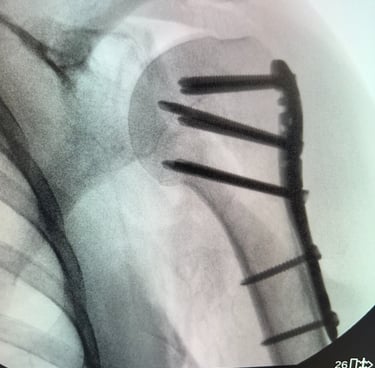

Mi occupo del trattamento traumatico sia in forma conservativa sia chirurgica. Tratto fratture, lussazioni, lesioni dei legamenti e dei tendini, con l’obiettivo di ripristinare la funzionalità articolare, ridurre il dolore e favorire un rapido ritorno alle attività quotidiane e sportive.